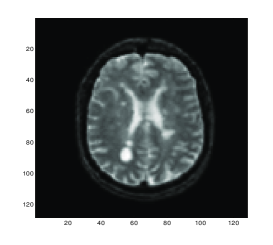

5.2 Test 2: A Pair of Brain MR Images

We take as Test 2 a pair of medical images of size 256×256256256256\times 256 from the Internet Brain Segmentation Repository (IBSR) http://www.cma.mgh.harvard.edu/ibsr where 20 normal MR brain images and their manual segmentations are provided. We choose the particular pair of individuals with different sizes of ventricle to illustrate a large deformation problem. Figure 3 shows the test images and the registration results using Gaussian curvature model. We can see that the model is able to solve real medical problems involving large deformations, which is particularly important for atlas construction in medical applications.

Refer to caption

(a) T𝑇T

(b) R𝑅R

(c) TR𝑇𝑅T-R

(d) 𝒙+𝒖(𝒙)𝒙𝒖𝒙\bm{x}+\bm{u}(\bm{x})

(e) T(𝒙+𝒖(𝒙))𝑇𝒙𝒖𝒙T(\bm{x}+\bm{u}(\bm{x}))

(f) T(𝒙+𝒖(𝒙))R𝑇𝒙𝒖𝒙𝑅T(\bm{x}+\bm{u}(\bm{x}))-R

Figure 3: Test 2: A pair of Brain MR images. Illustration of the effectiveness of Gaussian curvature with real medical images. On the top row, from left to right: (a) template, (b) reference and (c) the difference before registration. On the bottom row, from left to right: (d) the transformation applied to a regular grid, (e) the transformed template image and (f) the difference after registration. As can be seen from the result (e) and the small difference after registration (f), Gaussian curvature can be applied to real medical images and is able to obtain good results.